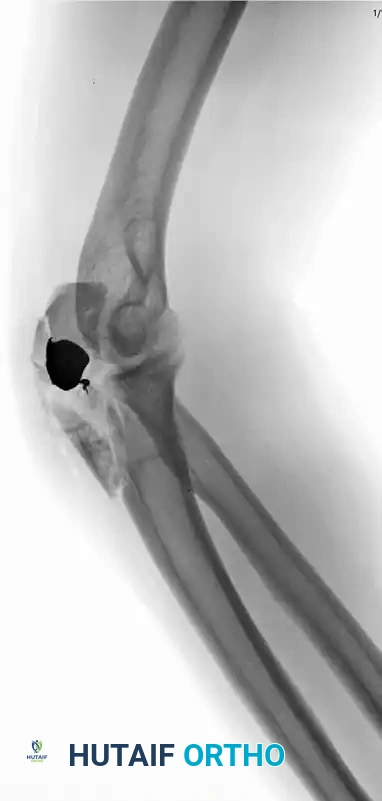

RADIAL HEAD AND NECK FRACTURES ASSOCIATED WITH ELBOW DISLOCATION

The management of radial head and neck fractures in the setting of an acute elbow dislocation remains one of the most challenging paradigms in orthopedic traumatology. The radial head is a critical secondary stabilizer of the elbow joint, functioning synergistically with the coronoid process to resist posterior translation and valgus stress. When the primary ligamentous restraints (the medial and lateral collateral ligaments) are disrupted during a dislocation, the osseous architecture of the radial head becomes the primary buttress against joint subluxation.

Treatment of these complex injuries is historically controversial, but modern biomechanical understanding dictates a strict adherence to restoring joint stability. Open Reduction and Internal Fixation (ORIF) of radial head fractures is always preferable to excision if the radial head is anatomically salvageable (typically defined as fewer than three articular fragments without severe metaphyseal comminution).

If the radial head is deemed unsalvageable and must be excised, the surgeon must acutely address the resulting valgus and posterolateral rotatory instability. In this scenario, the medial collateral ligament (MCL) and the flexor-pronator mass must be meticulously repaired.

Historically, Broberg and Morrey recommended early, complete excision of the radial head for type III (comminuted) fractures, followed by immobilization for no longer than 4 weeks. However, in the setting of a concomitant elbow dislocation, simple excision often leads to catastrophic instability. Today, the use of a metallic radial head implant (arthroplasty) is strongly considered—and often mandated—if instability persists after the MCL and flexor-pronator mass have been repaired. The prosthesis acts as a crucial temporary or permanent spacer to maintain the lateral column length and provide a valgus buttress.